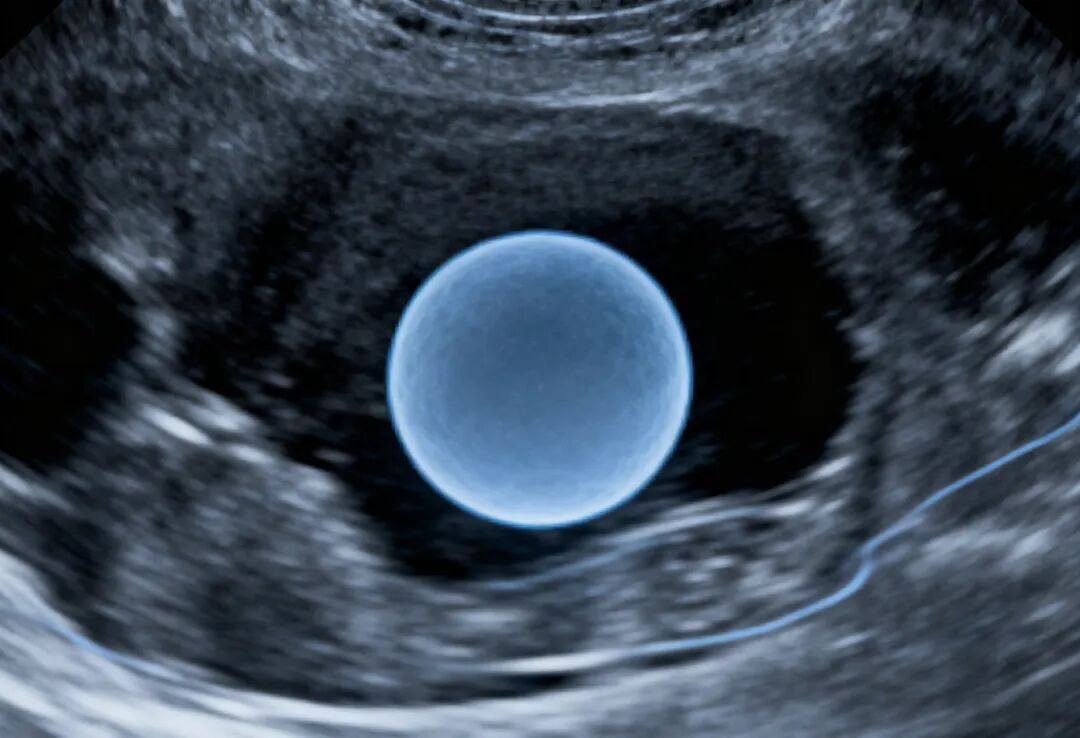

1. B超/HSG/超声造影:任何管腔扩张≥5 mm 或“腊肠样”无回声,都要警惕积水。